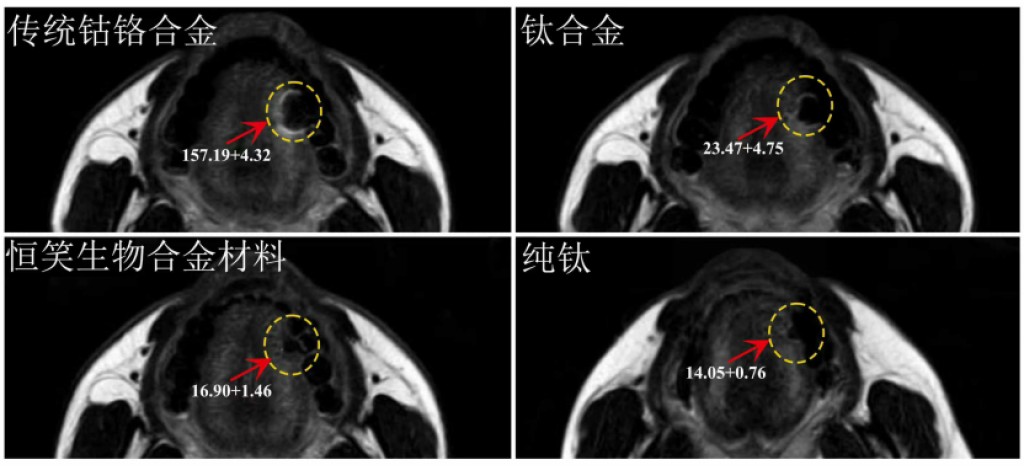

“戴了牙冠,是否影响做核磁?”——这是很多患者长久的顾虑。传统金属义齿在核磁检查中会产生明显伪影,干扰诊断。

图源:恒笑生物合金材料测试报告

恒笑®超微熔覆义齿凭借特殊的生物合金与超微熔覆工艺,实现了关键突破。根据上图报告可以看出,恒笑®超微熔覆义齿的核磁伪影面积和钛冠一致。众所周知,钛作为植入级材料,被广泛应用于牙科、骨科等领域,其稳定性和核磁兼容性已被反复验证。

恒笑®选用与植入级材料性能相当的高端生物合金,并通过超微熔覆技术进一步优化内部组织结构,真正实现不惧核磁,让患者安心佩戴,无忧核磁。